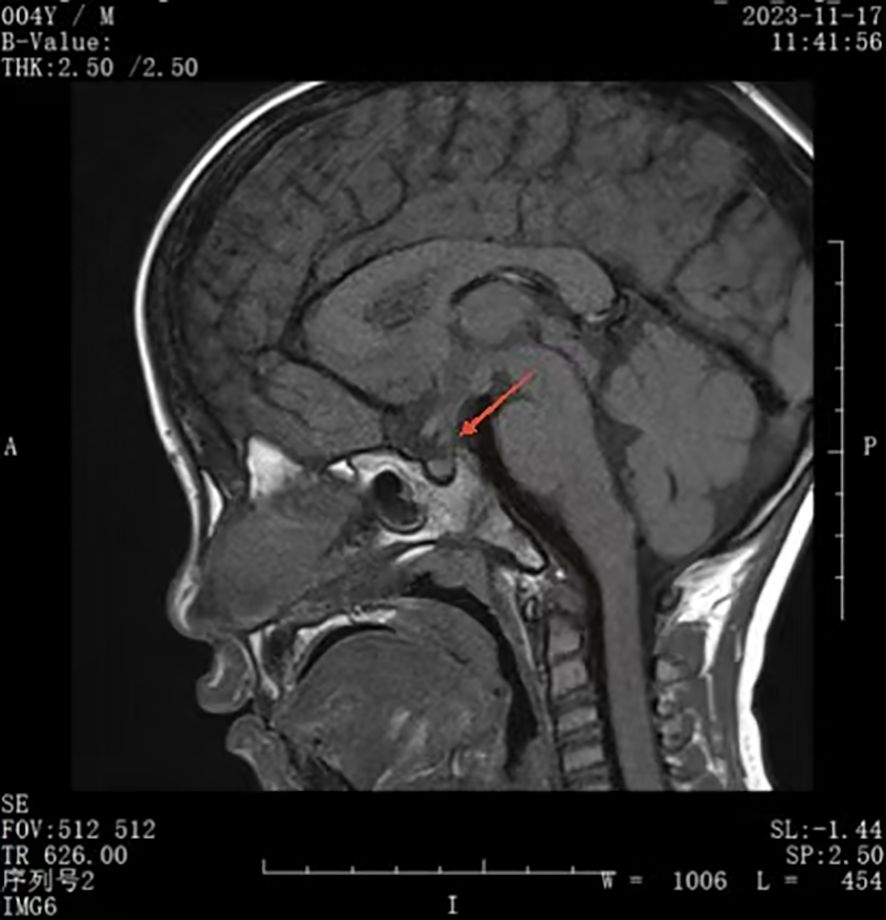

Rationale: SARS-CoV-2 infection can directly and indirectly affect the nervous system, including the hypothalamus and pituitary, and potentially cause IgG4-related hypophysitis. Patient concerns: A 4-year-old Chinese boy presented with arginine vasopressin deficiency (AVP-D, previously called 'central diabetes insipidus') and significant growth retardation. MRI indicated thickening of the pituitary stalk and alterations in the posterior pituitary. Diagnosis: The boy experienced polydipsia, polyuria, and enuresis 4 months after infection by SARS-CoV-2 and 2 months prior to presentation in June 2023. The diagnosis was IgG4-related hypophysitis, AVP-D, and growth hormone deficiency. Treatment with glucocorticoids and desmopressin led to significant resolution of symptoms and normalization of pituitary morphology. However, a second SARS-CoV-2 infection was followed by recurrence of polydipsia, polyuria, and thickening of the pituitary stalk. This recurrence led to a final diagnosis of IgG4-related hypophysitis caused by SARS-CoV-2 infection. Interventions: Glucocorticoids and desmopressin alleviated the AVP-D. Growth hormone and a diet and exercise plan were recommended to manage his short stature. We plan to conduct a functional assessment of the gonadal axis after he is 6 years old. Outcomes: After 18 months, the polydipsia and polyuria were controlled, and an MRI showed significant thinning of the pituitary stalk. This is the first reported case of lgG4-related hypophysitis in a Chinese boy infected with SARS-CoV-2. Lessons: We successfully controlled clinical symptoms, but further follow-up observations are needed to assess recovery. Although the role of SARS-CoV-2 infection in this patient's condition is only suggestive, other reports have described a relationship between SARS-CoV-2 infection and lgG4-related hypophysitis.